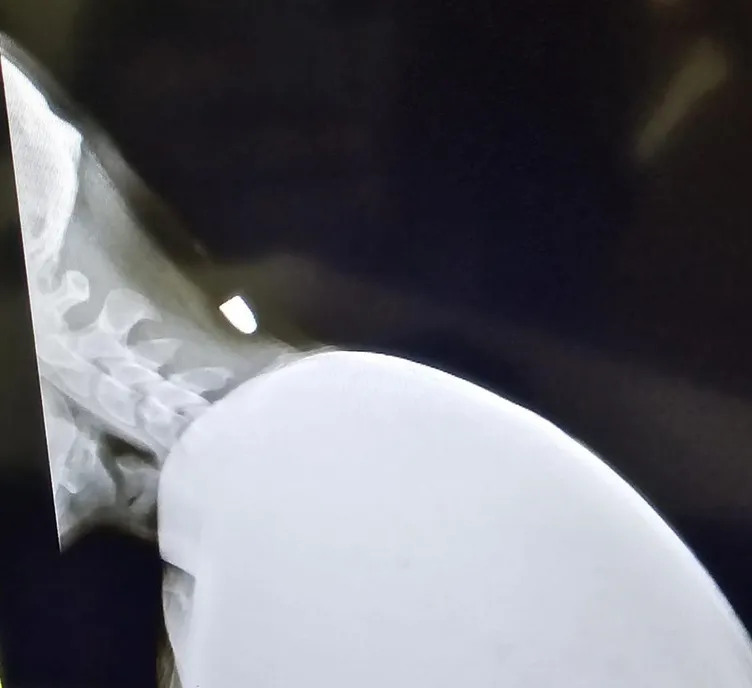

Hastanede yapılan müdahalelerde Yavuz’a ensesine mermi isabet ettiği tespit edildi. Geçen Pazartesi günü ameliyat olan Yavuz’un ensesindeki mermi 40 dakikalık ameliyatla çıkarıldı. Hastaneden taburcu edilen Yavuz’un sağlık durumu gün geçtikçe iyiye gidiyor. Polis ekipleri de konuyla ilgili inceleme başlattı.

Arkadaşlarıyla otururken yorgun merminin isabet ettiğini dile getiren Yunus Emre Yavuz, “İşte çalışıyorduk ve mola verdik. Akşam 19:30 sularında otururken biraz eğildim. Eğildiğim anda merminin düşmesi bir oldu. Biri sanki sertçe sopayla vurmuş gibi hissettim. Arkadaşlar yaraya baktığında kurşun olduğunu gördüler. Hastaneye götürdüler. Röntgen ve filmlere bakıldığında mermi olduğu anlaşıldı. Hastane sürecinde; röntgen ve MR filmleri çekildikten sonra ameliyat olmalısın dediler. Geçen pazartesi ameliyata girdim ve 40 dakika sürdü. Şükürler olsun sağlam çıktım. Kurşunu da incelenmesi için Adana’ya gönderildi. Zorlu bir süreç oldu ama atlattık” dedi.

Merminin şah damarının 2 santimetre yakınına isabet ettiğini Yavuz, “Ölümden döndüm. Ben değil başkası da olabilirdi veya ölebilirdim. Ben ölmedim ama başkasının başına gelip ölebilirdi. Kurşun şah damarının 2 cm yanındaydı ve biraz daha derine inseydi felç kalacaktım veya morgda olacaktım. Çocukluk hayalim asker olmaktı.